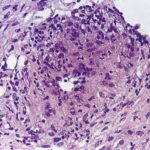

Histopathology . Pyoderma gangrenosum exhibits a dichotomous tissue reaction, showing central necrotizing suppurative inflammation, usually with ulceration, and a peripheral lymphocytic vascular reaction comprising perivascular and intramural lymphocytic infiltrates, usually without fibrin deposition or mural necrosis . Transitional areas show neutrophils in a loose cuff around the angiocentric lymphocytic infiltrates, defining a mixed lymphocytic and neutrophilic vascular reaction termed a Sweet’s-Iike vascular reaction . Bullous lesions may also demonstrate a Sweet’s-like vascular reaction with perivascular disintegrating neutrophilic infiltrates and hemorrhage without mural necrosis or luminal fibrin deposition. At variance with Sweet’s syndrome is destruction of the connective tissue framework with resultant tissue pathergy . Although a leukocytoclastic vasculitis may be observed in areas of maximal tissue pathology, pyoderma gangrenosum does not reflect a primary vasculitis . In some cases a necrotizing pustular follicular reaction may be the central nidus of the lesion, particularly in the vesicular pustular variant associated with ulcerative colitis or hepatobiliary disease. In the superficial granulomatous variant, florid pseudoepitheliomatous hyperplasia may be observed along with the intraepithelial and superficial dermal suppurative granulomatous inflammation with admixed plasma cells and eosinophils . Gases of pyoderma gangrenosum associated with Grohn’s disease may have areas of granulomatous inflammation . |